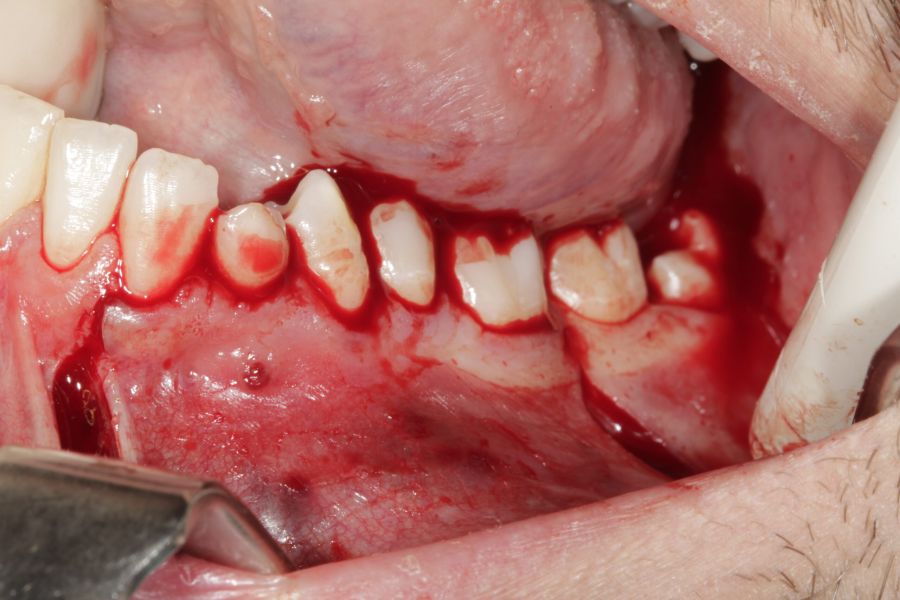

El tratamiento quirúrgico se llevó a cabo bajo sedación combinada con anestesia local de los nervios alveolar inferior, nervio lingual y mentoniano. Se realizó un acceso vestibular con una incisión de Newman (intrasulcular festoneada marginal a espesor total, con una descarga vertical a nivel de la cara mesial del incisivo lateral y distal del primer molar), seguida de un despegamiento mucoperióstico, procediendo a la visualización del foramen mentoniano; posteriormente se llevó a cabo una ostectomía con el fin de visualizar la lesión de la forma más amplia posible, observándose el canino mandibular junto a la cápsula quística por lo que se procedió a la extracción dentaria, bajo control visual del nervio mentoniano, para facilitar la enucleación completa y cuidadosa. Tras la eliminación de la cápsula quística se hizo un legrado cuidadoso de la cavidad residual, evitando el mismo sobre la zona basal con el fin de evitar lesionar el nervio dentario inferior. Una vez finalizada la intervención se procedió a reposicionar el colgajo mucoperióstico, suturando de forma hermética mediante sutura monofilamento de 4-0 (Figuras 5-12).